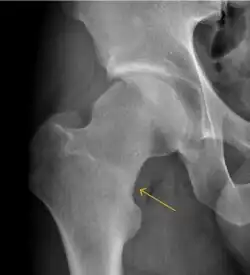

Plain radiography allows us to categorize the hip as normal or dysplastic or with impingement signs (pincer, cam, or a combination of both). Besides these, pathologic processes like osteoarthritis, inflammatory diseases, infection, or tumors can also be identified (Figure 1).[1]

Figure 1.

-

Radiography in normal hip -

X-ray in pincer impingement type of hip dysplasia -

X-ray of cam -

Hip in osteoarthritis -

Septic arthritis

X-ray in pediatrics